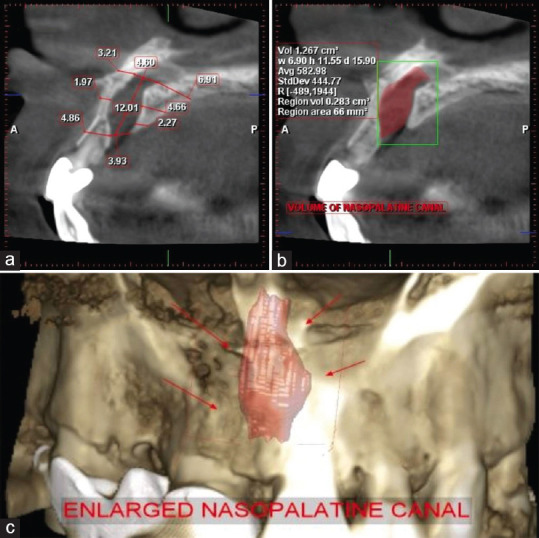

The incisive foramen is also called as nasopalatine foramen. It is a funnel-shaped opening in the anterior maxilla which opens immediately behind the central incisor teeth through which nasopalatine blood vessels and nerves pass. The incisive foramen is continuous with the incisive canal or nasopalatine canal (NPC). Variations in size, shape, position, and number of NPCs exist. Anatomical variations in NPC cannot be appreciated on two-dimensional radiographs. A case of anatomical variation of the nasopalatine canal misdiagnosed as a periapical cyst is discussed.